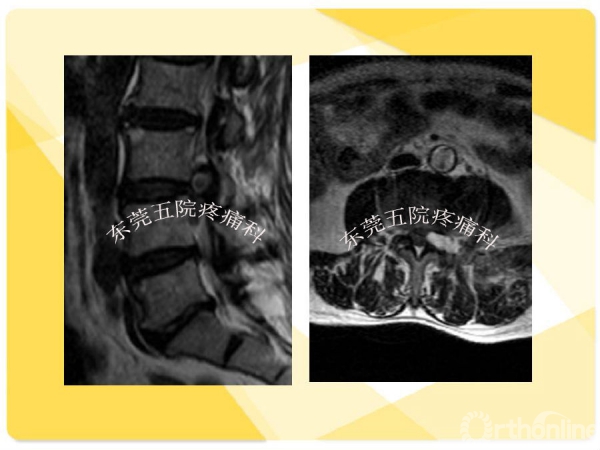

如何在椎间孔镜术前有效预防并发症的发生?如果不幸发生了该如何快速准确地处理?广东省东莞市第五人民医院疼痛科康健主任医师为大家分享了他的经验——